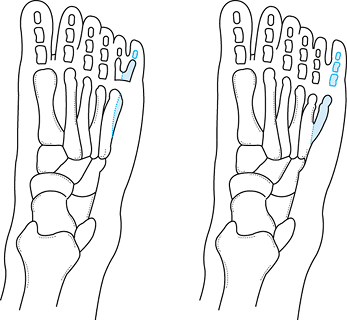

If performing a Lichtblau osteotomy (Fig. 167.2A) (17),

resect the distal portion of the os calcis to cancellous bone, using a

small osteotome. This shortens the calcaneus at the same level as the

talonavicular joint, allowing the midtarsal joint to translate easily

to a corrected position.

Figure 167.2. Lateral column shortening options for residual adduction deformity in clubfoot. A: Lichtblau osteotomy (resection distal os calcis). B: Cuboid decancellation. C: Evans procedure (calcaneocuboid fusion). -

If performing a cuboid decancellation (Fig. 167.2B), incise only enough of the capsule to identify the joint surface plane (10).

Use either a small osteotome or a curet to remove a wedge of bone from

the middle portion of the cuboid. In younger children, it is usually

easiest to simply curet out the ossific nucleus, leaving a shell of the

cartilaginous anlage. -

Compress the cuboid closed as the

released talonavicular joint is reduced. Check correction as for the

Lichtblau osteotomy, and adjust the medial release and bone resection

If performing a calcaneocuboid fusion (Evans procedure) (Fig. 167.2C),

curet or resect with an osteotome the articular surfaces of both

joints. Excessive resection is unnecessary, since the fusion reduces

lateral column growth potential and the midfoot will gradually abduct (10). -